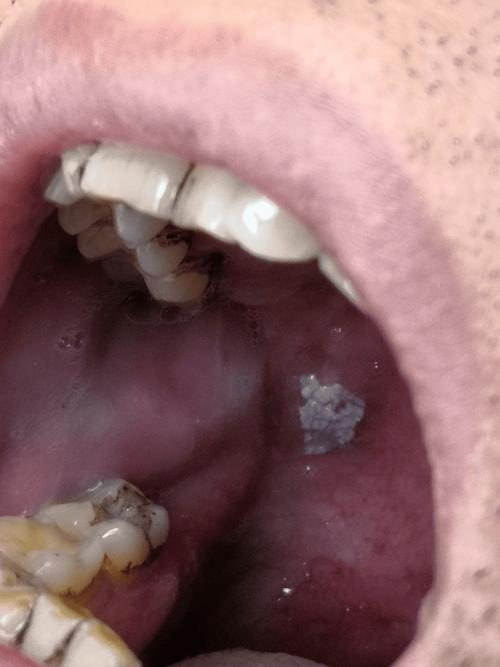

槟榔吃出口腔发白,几年了要紧吗?

看到您这个问题,我非常为您担心。口腔发白持续几年,并且有吃槟榔的习惯,这绝对是一个非常危险的信号,绝不能掉以轻心。

这很可能是口腔黏膜下纤维化的典型症状,而口腔黏膜下纤维化是公认的口腔癌的癌前病变。

- 典型表现:口腔黏膜(尤其是颊黏膜、牙龈、舌下)出现边界不清的白色或灰白色条纹、斑块,质地变硬,失去弹性。

- 时间跨度:您提到“几年了”,这个病程与OSF的发展过程非常吻合,这是一个慢性、渐进性的过程,从轻微症状到严重病变可能需要数年时间。